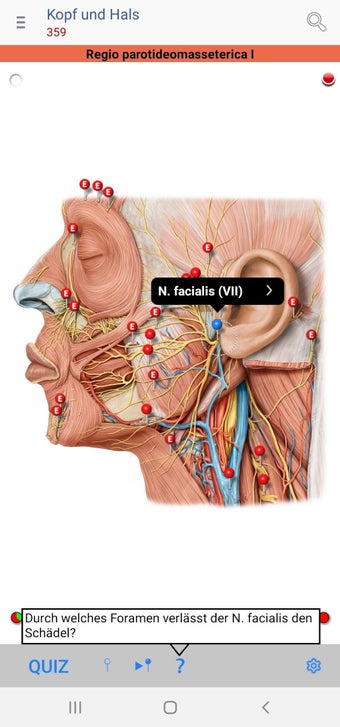

The app consists of different sections, each of which contains information about a specific part of the body. You will learn about the different organs, as well as the muscles, bones, and other important structures. You can test yourself with a unique quiz that consists of multiple-choice questions.